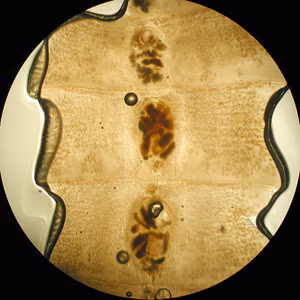

Diphyllobothriid eggs

Diphyllobothriid eggs are oval or ellipsoidal and range in size from 55 to 75 µm by 40 to 50 µm. There is an operculum at one end that can be inconspicuous, and at the opposite (abopercular) end is a small knob that can be barely discernible. The eggs are passed in the stool unembryonated. Although eggs of Adenocephalus pacificus are generally smaller than those of Dibothriocephalus spp. and Diphyllobothrium spp., there is a degree of overlap and thus species identification based on eggs may not be reliable.

Mature diphyllobothriids are large tapeworms reaching 2—15 meters in length, with occasional larger specimens. The scolex always has two bothria (grooves). The general size and shape of the scolex may be subject to intraspecific variability, though some species-level differences have been described historically. Proglottids are broader than long, with a single genital pore that opens in the middle of the ventral surface; fully mature specimens may be comprised of a 2,000—5,000 proglottids. The ovaries are characteristically rosette-shaped.

Microscopic identification of eggs in the stool is the basis of family level diagnosis; genus level identification based on eggs is difficult due to overlap in morphological features. Eggs are usually numerous and can be demonstrated without concentration techniques. Identification of proglottids passed in the stool is also of diagnostic value.